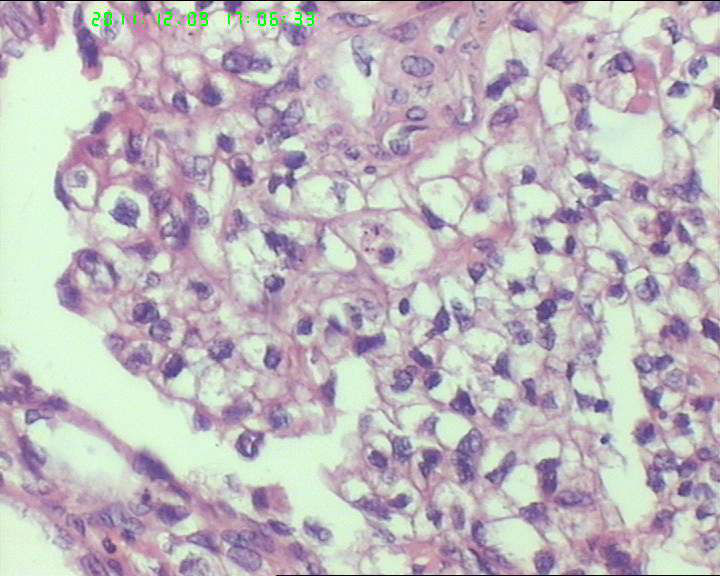

各位老师,会诊一下,49岁卵巢肿物,到底是什么呢?

盆腔包块4个月,13*8*7cm 大小,囊实性,实性区菜花状、灰白质脆,局部半透明。

1. 透明细胞癌

2. 卵黄囊瘤